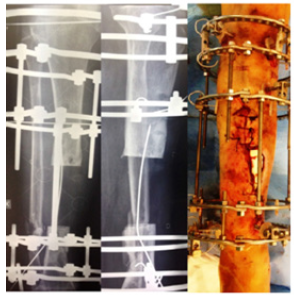

Case No 2

A male aged 60 had motor vehicle accident and sustained open fracture (Gustilo and Anderson type 3 b) of the tibia. Initially, he managed in another hospital with unplaster external fixator with screws in tibia and Kirschner wire in fibula. As there was skin loss so flap was applied over it. A few days late the flap was failed and there was pouring pus coming out of wound. In the first step he was referred to infective medicine unit of our hospital for infection control. A lot of antibiotics has been tried but insane. They have requested our unit for help in managing to eradicate infection. All antibiotics were stopped debridement with wound excision was done but it did not heal. Then all the implants were removed and daily dressing was advised to control infection but no improvement. Finally a resection of the nine centimeter of infected segment of bone done with application of Ilizarov fixator proximal osteotomy for bone transport. No antibiotics were used in this procedure. Skin loss were coverd without any procedure after application of Ilizarov that controlled the infection. With Ilizarov there is darmatotaxis which cover the skin loss. After few follow ups of bone transport the patient felt severe pain when he rotated the nuts. On examining the patient, everything was found normal except the lateral radiograph, which showed the transporting bone was deviated from its path. Deviation was corred with horizontal rods while the transport was stopped. In the next follow up visit we saw new bone formation within the gap. We stoped everything for the gap to be healed spontaneaouly without transport. In this patient, a 5 centimeter bone has been transported (Figures 7-12).